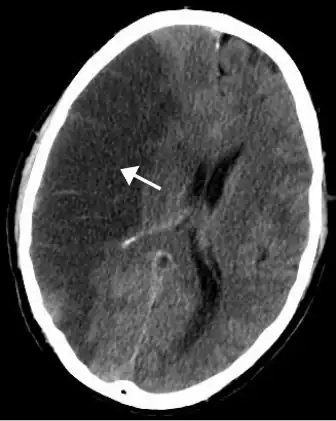

| CT scan of the brain showing a prior right-sided ischemic stroke from blockage of an artery. Changes on a CT may not be visible early on.[1] | |

The main risk factor for stroke is high blood pressure.[6] Other risk factors include tobacco smoking, obesity, high blood cholesterol, diabetes mellitus, a previous TIA, end-stage kidney disease, and atrial fibrillation.[2][6][7] An ischemic stroke is typically caused by blockage of a blood vessel, though there are also less common causes.[12][13][14] A hemorrhagic stroke is caused by either bleeding directly into the brain or into the space between the brain's membranes.[12][15] Bleeding may occur due to a ruptured brain aneurysm.[12] Diagnosis is typically based on a physical exam and supported by medical imaging such as a CT scan or MRI scan.[8] A CT scan can rule out bleeding, but may not necessarily rule out ischemia, which early on typically does not show up on a CT scan.[9] Other tests such as an electrocardiogram (ECG) and blood tests are done to determine risk factors and rule out other possible causes.[8] Low blood sugar may cause similar symptoms.[8]

CT scans may not detect an ischemic stroke, especially if it is small, of recent onset, or in the brainstem or cerebellum areas. A CT scan is more to rule out certain stroke mimics and detect bleeding.[9]